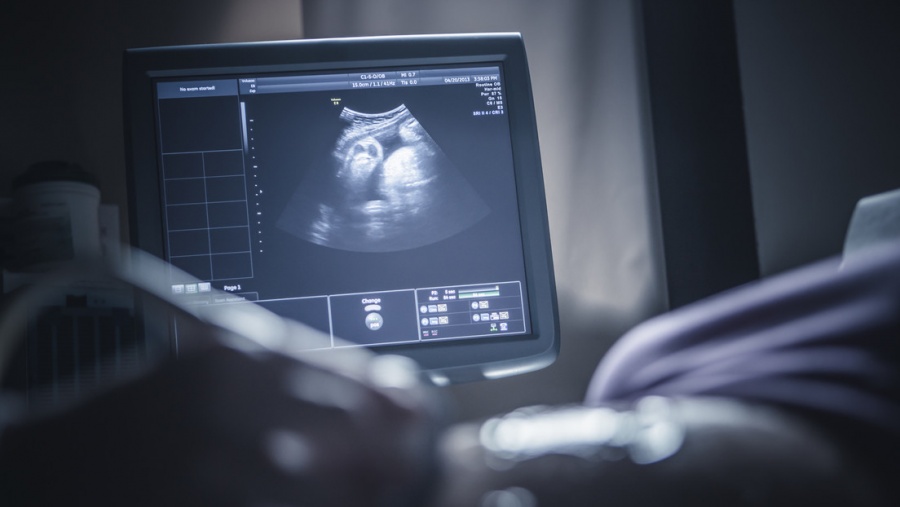

Una mujer embarazada de Egipto se ha topado con la noticia de que espera nueve hijos, un caso médicamente excepcional, según un diagnóstico ecográfico reportado por la cadena Al Arabiya.